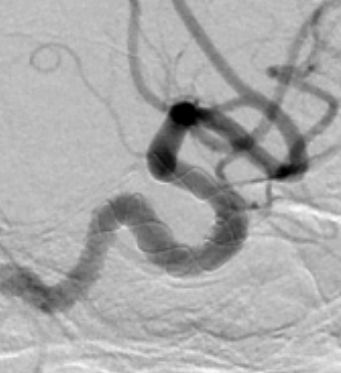

入院后行DSA检查明确右侧颈内动脉眼动脉后下方囊状动脉瘤样影,大小约1.09mm×6.53mm,宽基底,其下方见两个小囊状突起,左侧颈内动脉眼动脉后方及虹吸段均可见小囊状突起。考虑颅内多发动脉瘤。

右侧颈内动脉眼段巨大动脉瘤